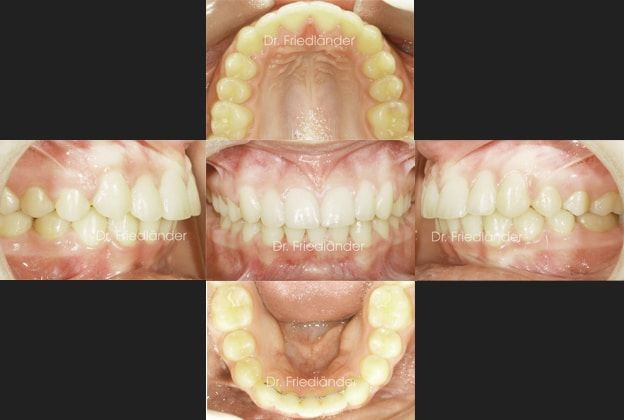

14 meses más tarde el tratamiento ya estaba terminado, se puede observar que conseguimos todos los objetivos propuestos; mejorar la salud de las encías, conseguir clase I en ambos lados y mejorar la mordida profunda.

En las siguientes fotografías se puede observar como ha mejorado la salud de las encías. Las raíces de los dientes inferiores ya no esta tan salidas fuera del hueso.